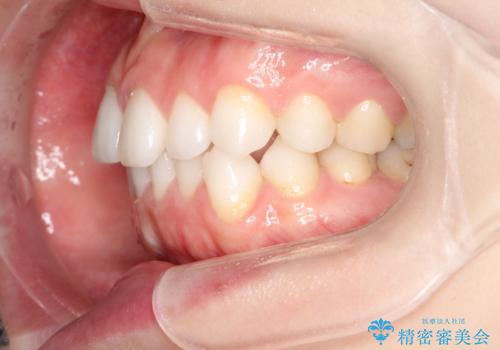

前歯のがたつきをインビザラインで目立たず矯正治療

- 上下の前歯のがたつきを主訴に来院されました。

目立たない装置がご希望で、インザラインによるマウスピース矯正にて治療を行うこととなりました。